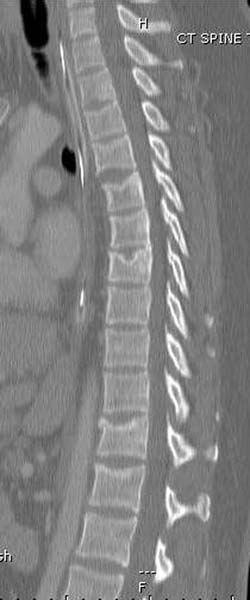

Перелом позвоночника и боковую компрессию таза отнесли к стабильным переломам и не стали форсировать события до лучших времен...

После спадения отека на стопе произведена фиксация тарана. Кстати, коллеги пересмотрели первоначальную консультацию по позвоночнику и на двух уровнях провели фиксацию. Из-за длительного постельного режима без нагрузки таз не стали оперировать...